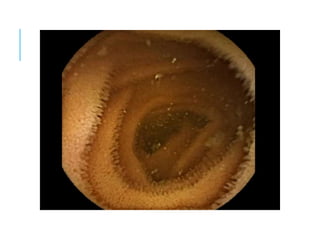

ENDOSCOPY

ESOPHAGUS